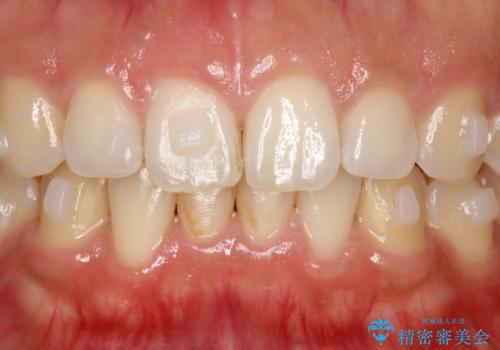

このプラーク(歯垢)にはたくさんの細菌が潜んでおり、虫歯や歯周病・口臭などの最大の原因です。そのため、毎日の歯磨きでプラーク(歯垢)をキレイに取り除くことが、健康な歯を保つためには欠かせません。

しかし、プラークは歯の色と似ているため、見ただけでは付着しているかどうかがハッキリとは分かりません。

染め出し液を使ってプラークを染め出すことにより、普段の歯みがきで磨き残している場所を目で確かめることができます。

日々の歯磨きを上達するには、まずどこが磨けていないか認識することが大切です。